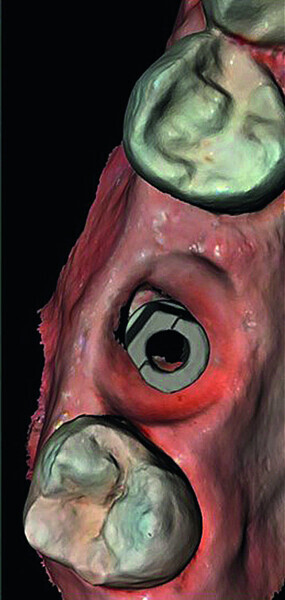

Digital workflow and application of PRF and ozone therapy in oral rehabilitation